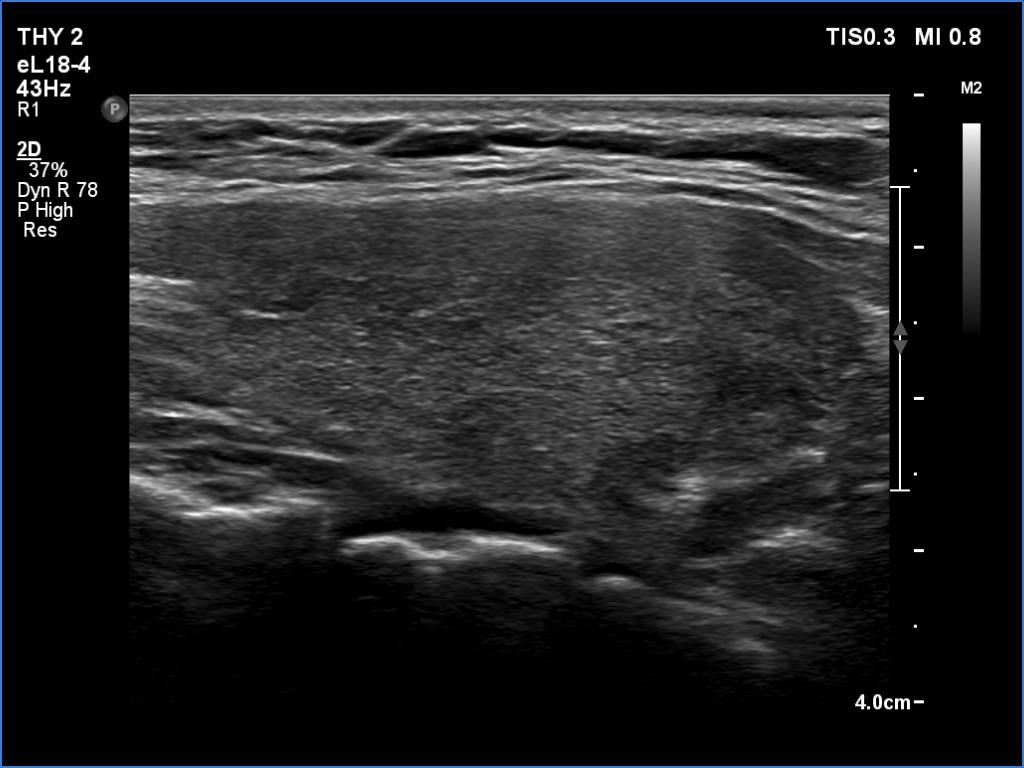

Right lobe, longitudinal scan

Right lobe, longitudinal scan. The hypoechoic areas correspond to more active foci of the underlying autoimmune process.